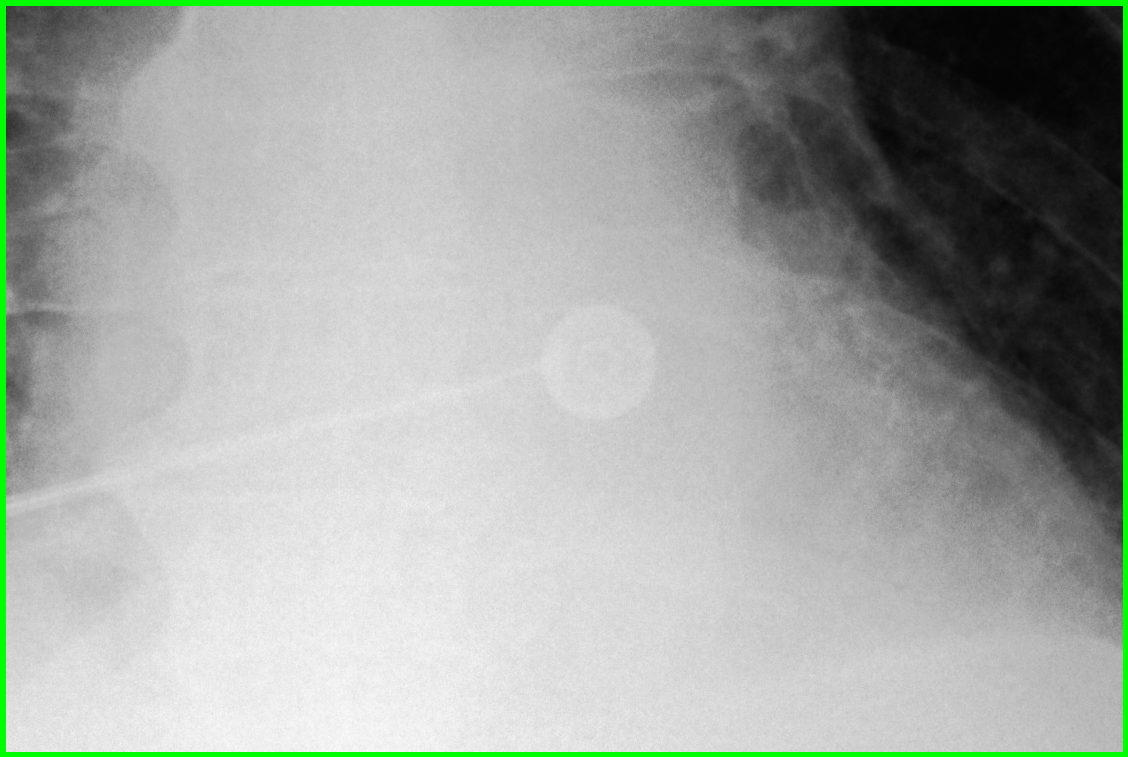

Figure 2: Examples of the results obtained by our best two models. The overall chest X-ray image is shown alongside two anatomical regions. The predictions from best performing models are compared against the ground-truth labels.

The CheXGCN model outperforms the other two baselines but is also limited because it focuses on one section and uses label dependencies to learn the relationship between the labels, while ignoring the relationships between the anatomical regions of the chest X-ray image. In Table 2, we visualize the output from both the CheXGCN model and our AnaXNet model. The CheXGCN model had difficulty predicting small anatomical regions like the costophrenic angles, while our model had additional information from the remaining anatomical regions, which helped in its prediction. Also the CheXGCN model struggled with enlarged cardiac silhouette label because information from the surrounding labels is needed in order to accurately tell if the heart is enlarged.